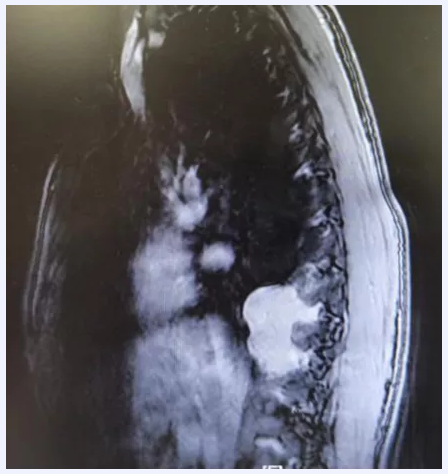

这种肿瘤“脾气”很“臭”——手术刀刚“挨”上它,它就让患者的血压一路飙升;一旦切掉它,它又会“遥控”患者的血压一路暴跌,危及生命,被称为“手术中的隐形杀手”。不久前,经过多学科反复会诊和一个月的术前准备,在北京天坛医院的手术室里,手术医生和麻醉医生一起,联手与这样一个罕见地长在胸腔的异位嗜铬细胞瘤展开“斗智斗勇”的较量。

患者是一位青年男性,因为“后纵膈肿物”住院,并准备进行胸腔镜下肿物切除术。“从麻醉诱导到手术开始一切都挺顺利的,可是当外科医生准备分离肿瘤的时候,意外发生了。”麻醉科主任医师金旭发现,患者的动脉血压监测的数值骤升至260/130mmHg,立即提醒术者停止刺激肿瘤,随后患者的血压逐步恢复到正常。

患者有高血压、糖尿病病史,在手术时循环出现剧烈波动,金旭怀疑,这位患者很可能患有内分泌功能副神经节瘤(异位嗜铬细胞瘤)。“这种肿瘤发病数量本身就不多,发病多在肾上腺或腹部,长在胸腔的非常罕见。”金旭说,如果准备不充分,这种肿瘤手术死亡率非常高,堪称手术中的“隐形杀手”。医院胸外科主任魏博和麻醉科主任韩如泉立即对这名患者情况进行联合会诊,一致认为继续手术患者死亡可能性较大,经过充分与患者家属沟通,决定暂停手术,积极进行术前准备。